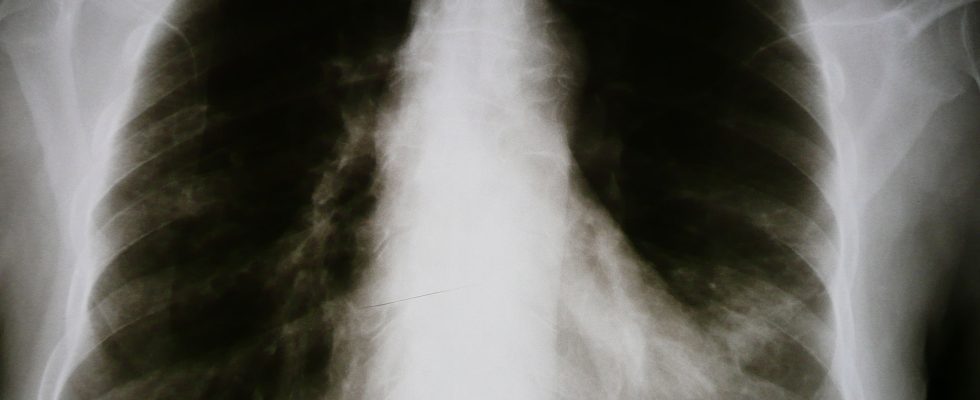

Woman dies of lung cancer after missed diagnosis

New York — A woman from Brooklyn, NY died from complications of lung cancer after doctors at the hospital delayed diagnosis of her deadly condition. Family of the victim say that the hospital’s misdiagnosis was due to not following up on a suspicious finding in an x-ray several years earlier. A small nodule or mass was spotted on a chest x-ray but her doctors failed to properly evaluate this, delaying her cancer diagnosis for over two years. Reports show that the doctors working in the New York City owned hospital were negligent by not fully reading and acting on the x-ray report from the radiologist, which pointed out the suspicious spot and recommended specific follow-up instructions. The missed diagnosis of her lung cancer allowed the disease to continue growing until it metastasized, spreading to her other lung, liver, spine and brain. The original hospital error was compounded when subsequent clinic doctors kept treating the woman’s cough and difficulty breathing as asthma. Those doctors never ordered another chest x-ray or properly reviewed the original one.